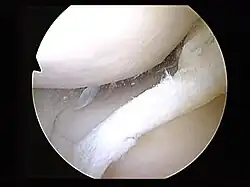

-

MRI of right knee revealing intra-articular and bucket-handle medial meniscus tear with the displaced fragment located in the intercondylar notch. -